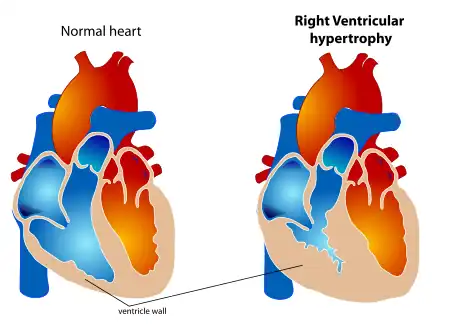

Right ventricular (RVH) is a condition defined by an abnormal enlargement of the cardiac muscle surrounding the right ventricle. The right ventricle is one of the four chambers of the heart. It is located towards the lower-end of the heart and it receives blood from the right atrium and pumps blood into the lungs.

.png.webp) RV inflow view showing marked right ventricular hypertrophy

RV inflow view showing marked right ventricular hypertrophy Hexaxial reference system

Echocardiography can be used to directly visualise right ventricular wall thickness. The preferred technique is the trans-oesophageal approach giving a view of 4 chambers. The normal thickness of a right ventricular free wall ranges from 2-5 millimetres, with a value above 5 mm considered to be hypertrophic.[11]